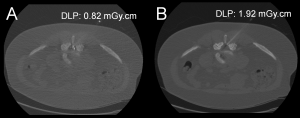

The needle tip visibility did not differ significantly between the two groups (p = 1.0, Chi-square test) (Figures 2, 3, 4, and 5). The needle tip was visible in nearly every patient in this study (170 out of 171).